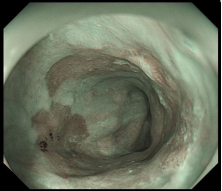

图示:结肠高分化腺癌:镜下呈隆起病变,放大内镜观察:表面结构不规则,微血管扭曲、紊乱、不规则。